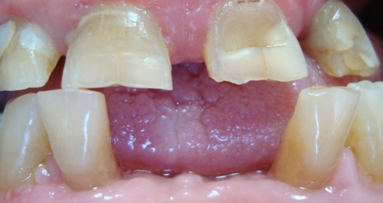

Application of a topical anaesthetic.

A 14-year-old female patient was referred to our department by the orthodontics unit because, at the end of fixed orthodontic treatment, she had developed gingival enlargement in the upper arch (Fig. 1), probably related to the fast closure of the spaces associated with very poor oral hygiene due to bleeding during toothbrushing. Just after the removal of the appliance, a topical anaesthetic (EMLA, AstraZeneca) was applied to the gingivae (Fig. 2) and a gingivectomy was performed using a diode laser (XD-2, Fotona) according to the technique of removal of the inter dental papillae (Fig. 3). The parameters used were as follows: a wavelength of 808 nm, 3 W in continuous wave, a 320 μm fibre in contact mode. The intervention had a duration of 375 seconds, and the patient did not feel any pain (Fig. 4). After the intervention, the patient did not take any kind of pain medication, and the healing process was completed in five days (Fig. 5).